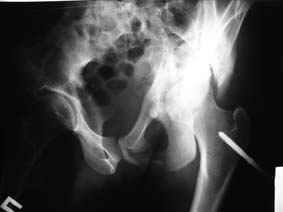

Все-таки надо бы начать не с КТ, а с обзорного снимка таза и косых проекций впадины.

Это обзорные и косые снимки

С уважением,